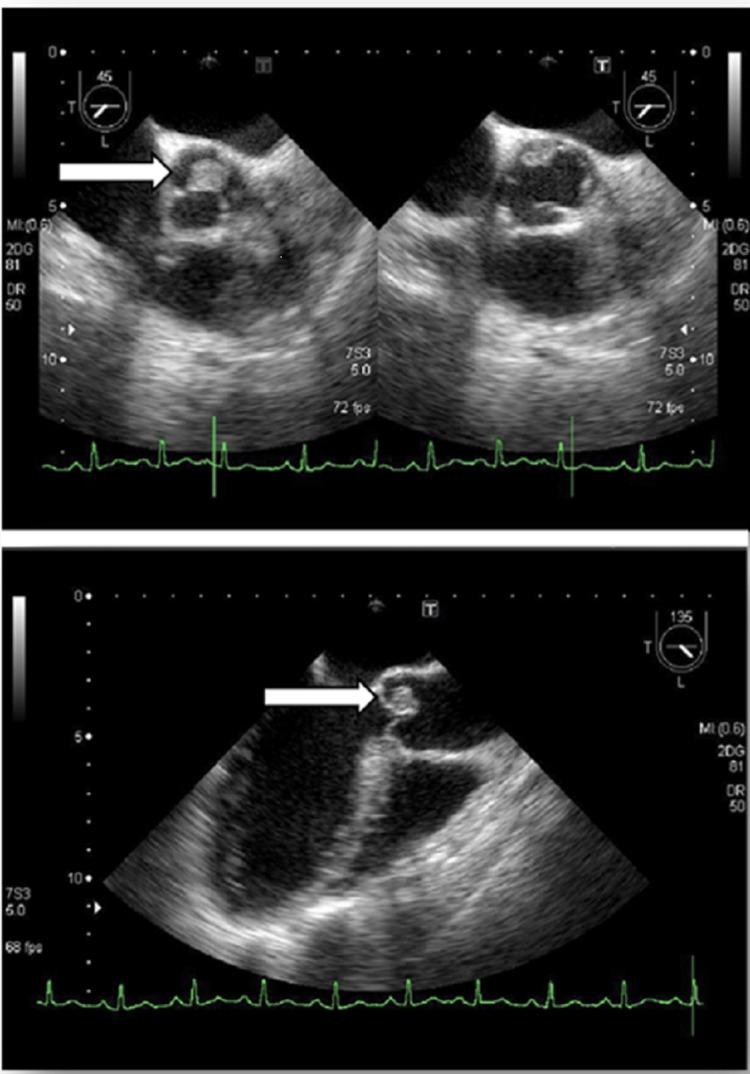

Secondary headache is a symptom of an underlying disease. Infective endocarditis (IE) is a serious infection of the heart tissue. Herein, we present a rare case of IE, with a secondary headache. The patient presented with persistent headache, fever of 39°C, myalgia, and painful erythema of the plantar surface of the foot. The headache progressively worsened over a few weeks. She was diagnosed with secondary headache, and sepsis was suspected. Blood culture revealed the presence of leading to a diagnosis of IE. Postoperatively, the patient recuperated without any complications. Headaches can be secondary to other conditions. Therefore, comprehensive assessment and accurate diagnosis are essential. Dentists must be aware that headache is a concomitant symptom of IE.

继发性头痛是潜在疾病的一种症状。感染性心内膜炎(IE)是心脏组织的一种严重感染。在此,我们报告一例罕见的伴有继发性头痛的感染性心内膜炎病例。患者表现为持续性头痛、39°C发热、肌痛以及足底疼痛性红斑。头痛在数周内逐渐加重。她被诊断为继发性头痛,并怀疑有败血症。血培养显示存在[此处原文缺失相关内容],从而确诊为感染性心内膜炎。术后,患者康复且无任何并发症。头痛可能继发于其他病症。因此,全面评估和准确诊断至关重要。牙医必须意识到头痛是感染性心内膜炎的伴随症状。